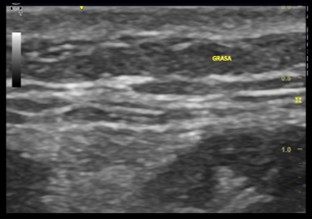

4. Tejido subcutáneo

Está formado por lóbulos de grasa separadas por tabiques o bandas de tejido conjuntivo. En la ecografía se demuestra con un fondo hipoecogénico de grasa y ecos hiperecogénicos lineales procedentes de la red tabicular de tejido conectivo.

Imagen ecográfica 4.1 Tejido subcutáneo abdominal.